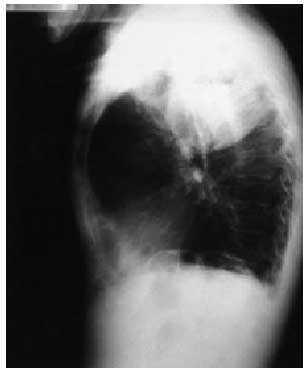

En la radiografía de tórax se observaba una masa cavitada que ocupaba la totalidad del lóbulo superior derecho (figs. 1 y 2).

Fig. 2.